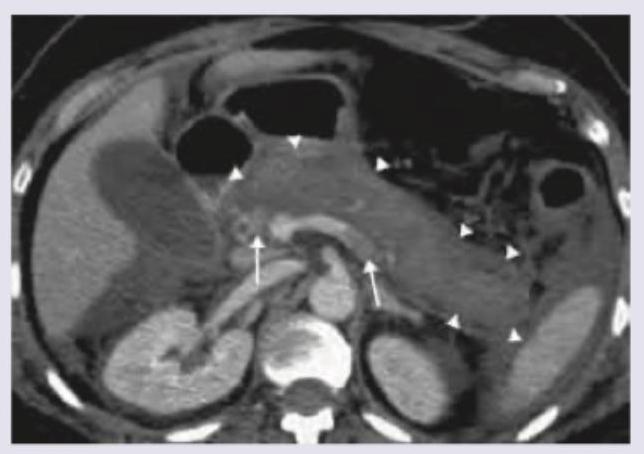

A 40-year-old alcoholic presents with severe epigastric pain and hemodynamic collapse. CT abdomen was performed after fluid resuscitation which shows: (Recent NEET Pattern 2016-17)

Explanation: ***Severe acute pancreatitis*** - The CT scan shows significant **peripancreatic fat stranding** and **fluid collections** (indicated by arrowheads), which are hallmark features of acute pancreatitis - The presence of **hemodynamic collapse** with extensive peripancreatic inflammatory changes indicates **severe acute pancreatitis** (previously called necrotizing pancreatitis) - Clinical context: **alcoholic patient** with severe epigastric pain and shock—classic presentation requiring ICU care - The **revised Atlanta classification** defines severe acute pancreatitis by the presence of organ failure (hemodynamic collapse = cardiovascular failure) *Acute pancreatitis* - While the CT undeniably shows acute pancreatitis, this option is **too non-specific** given the clinical severity - The presence of **hemodynamic collapse** (organ failure) by definition classifies this as **severe** acute pancreatitis, not simple acute pancreatitis - Missing the severity classification could lead to underestimation of disease gravity and inadequate management *Perforation peritonitis* - Would typically show **free intraperitoneal air** (pneumoperitoneum) on CT, which is absent here - The CT findings are specifically pancreatic: **peripancreatic inflammation and fluid collections**, not diffuse peritoneal contamination - While severe epigastric pain and collapse can occur with perforation, the imaging is diagnostic for pancreatic pathology *Pseudo-pancreatic cyst* - Pseudocyst is a **late complication** of acute pancreatitis, typically forming **4-6 weeks** after the initial attack - Represents a **mature, well-defined fluid collection** with a fibrous wall, not acute inflammatory changes - The patient's **acute presentation** with immediate pain and hemodynamic collapse, along with diffuse peripancreatic inflammatory changes (not a discrete encapsulated collection), excludes this diagnosis